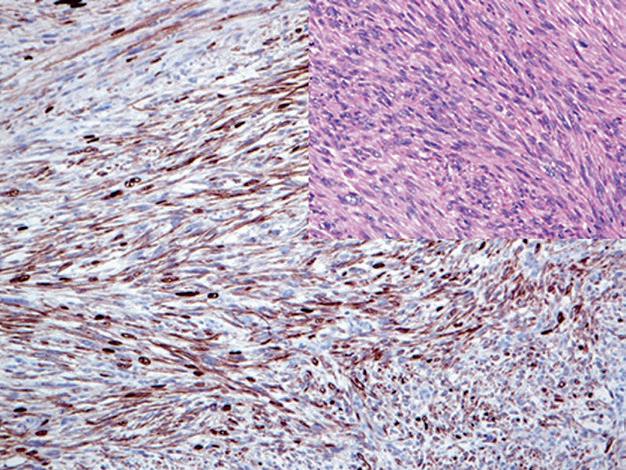

图2. 横纹肌肉瘤中,Myogenin(左)和MyoD1(右)在细胞核强阳性表达。

需要注意的是,这两种肌源性标记在非肿瘤性肌母细胞中均可为阳性,而这类细胞可见于修复性及萎缩性肌肉病变中。Myogenin和MyoD1的表达也曾报道于某些其他肿瘤,如韧带样瘤、婴儿型纤维肉瘤、Wilms瘤。Myogenin和MyoD1染色的解读中,仅有细胞核着色才能被视为阳性,其他着色方式(如胞质着色、细胞膜着色)都是无诊断意义的假象。